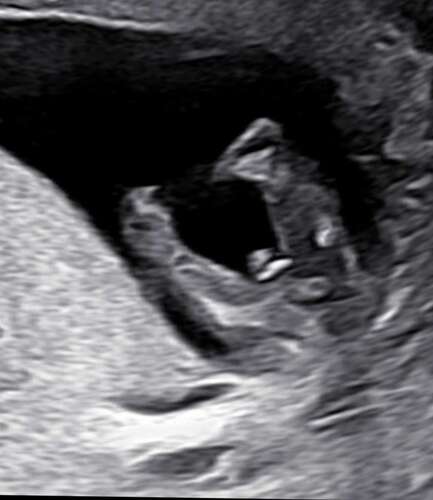

Zijkant 13+3 vorige post is van tussen de benen

Ja beide foto’s denk ik jongen

Jongetje! 💙